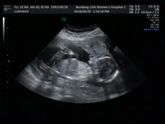

Второе УЗИ ?

За две недели заметно подросли 8-9 неделя ❤️ наше чудо ❤️